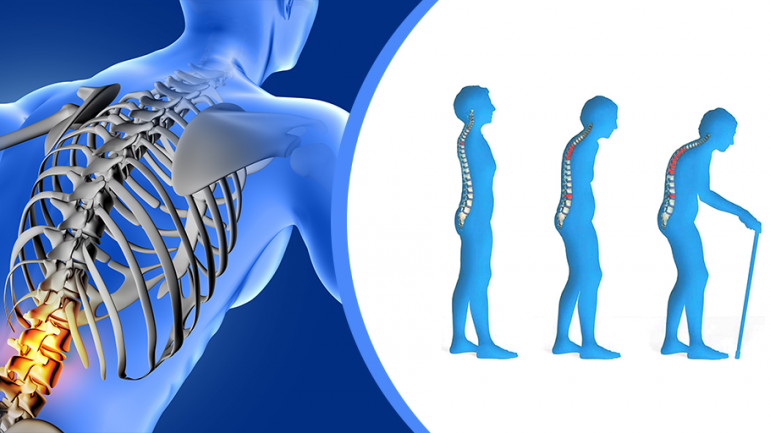

Οι επιζώντες των περισσότερων τύπων καρκίνου διέτρεχαν αυξημένο κίνδυνο κατάγματος οστών για αρκετά χρόνια μετά τον καρκίνο.